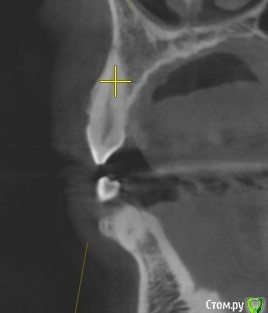

Tatiana72 Опубликовано 27 октября, 2020 Автор Поделиться Опубликовано 27 октября, 2020 Добрый вечер!Выкладываю скрины срезов Ссылка на исследованиеhttps://yadi.sk/d/ViQR0U6R2QjHzg Ссылка на комментарий

Дмитрий М Опубликовано 28 октября, 2020 Поделиться Опубликовано 28 октября, 2020 Добрый вечер!Выкладываю скрины срезовImage4.jpgImage5.jpgImage9.jpg Ссылка на исследованиеhttps://yadi.sk/d/ViQR0U6R2QjHzg не волнуйтесь всё хорошо, по КТ корень зуба не задетесть небольшой очаг разряжения на одном из апексов, обратитесь к стоматологу 1 Ссылка на комментарий